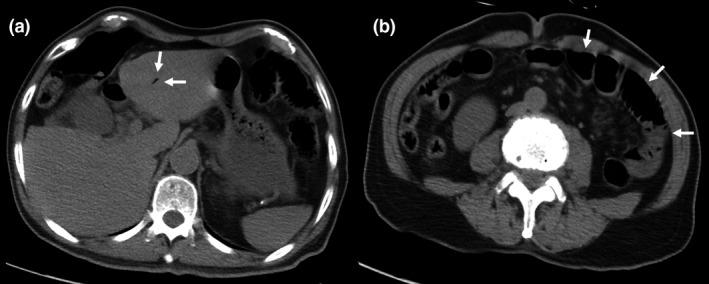

A 77-year-old man was transferred due to shock and disorder of consciousness. He was diagnosed with an HHS. We suspected intestinal ischemia due to a small amount of HPVG revealed by computed tomography (CT). Peritoneal signs were revealed after treatment for the HHS. Computed tomography was carried out again 5 h after admission, which showed a large amount of HPVG, remarkable bowel dilatation, and pneumatosis intestinalis. We performed an emergency laparotomy and resected the small bowel necrosis resulting from NOMI.

一名77岁男性因休克和意识障碍被转诊。他被诊断为HHS。由于计算机断层扫描(CT)显示少量HPVG,我们怀疑存在肠道缺血。在对HHS进行治疗后出现了腹膜刺激征。入院5小时后再次进行CT检查,结果显示大量HPVG、明显的肠扩张和肠壁积气。我们进行了急诊剖腹手术,切除了由NOMI导致的小肠坏死。